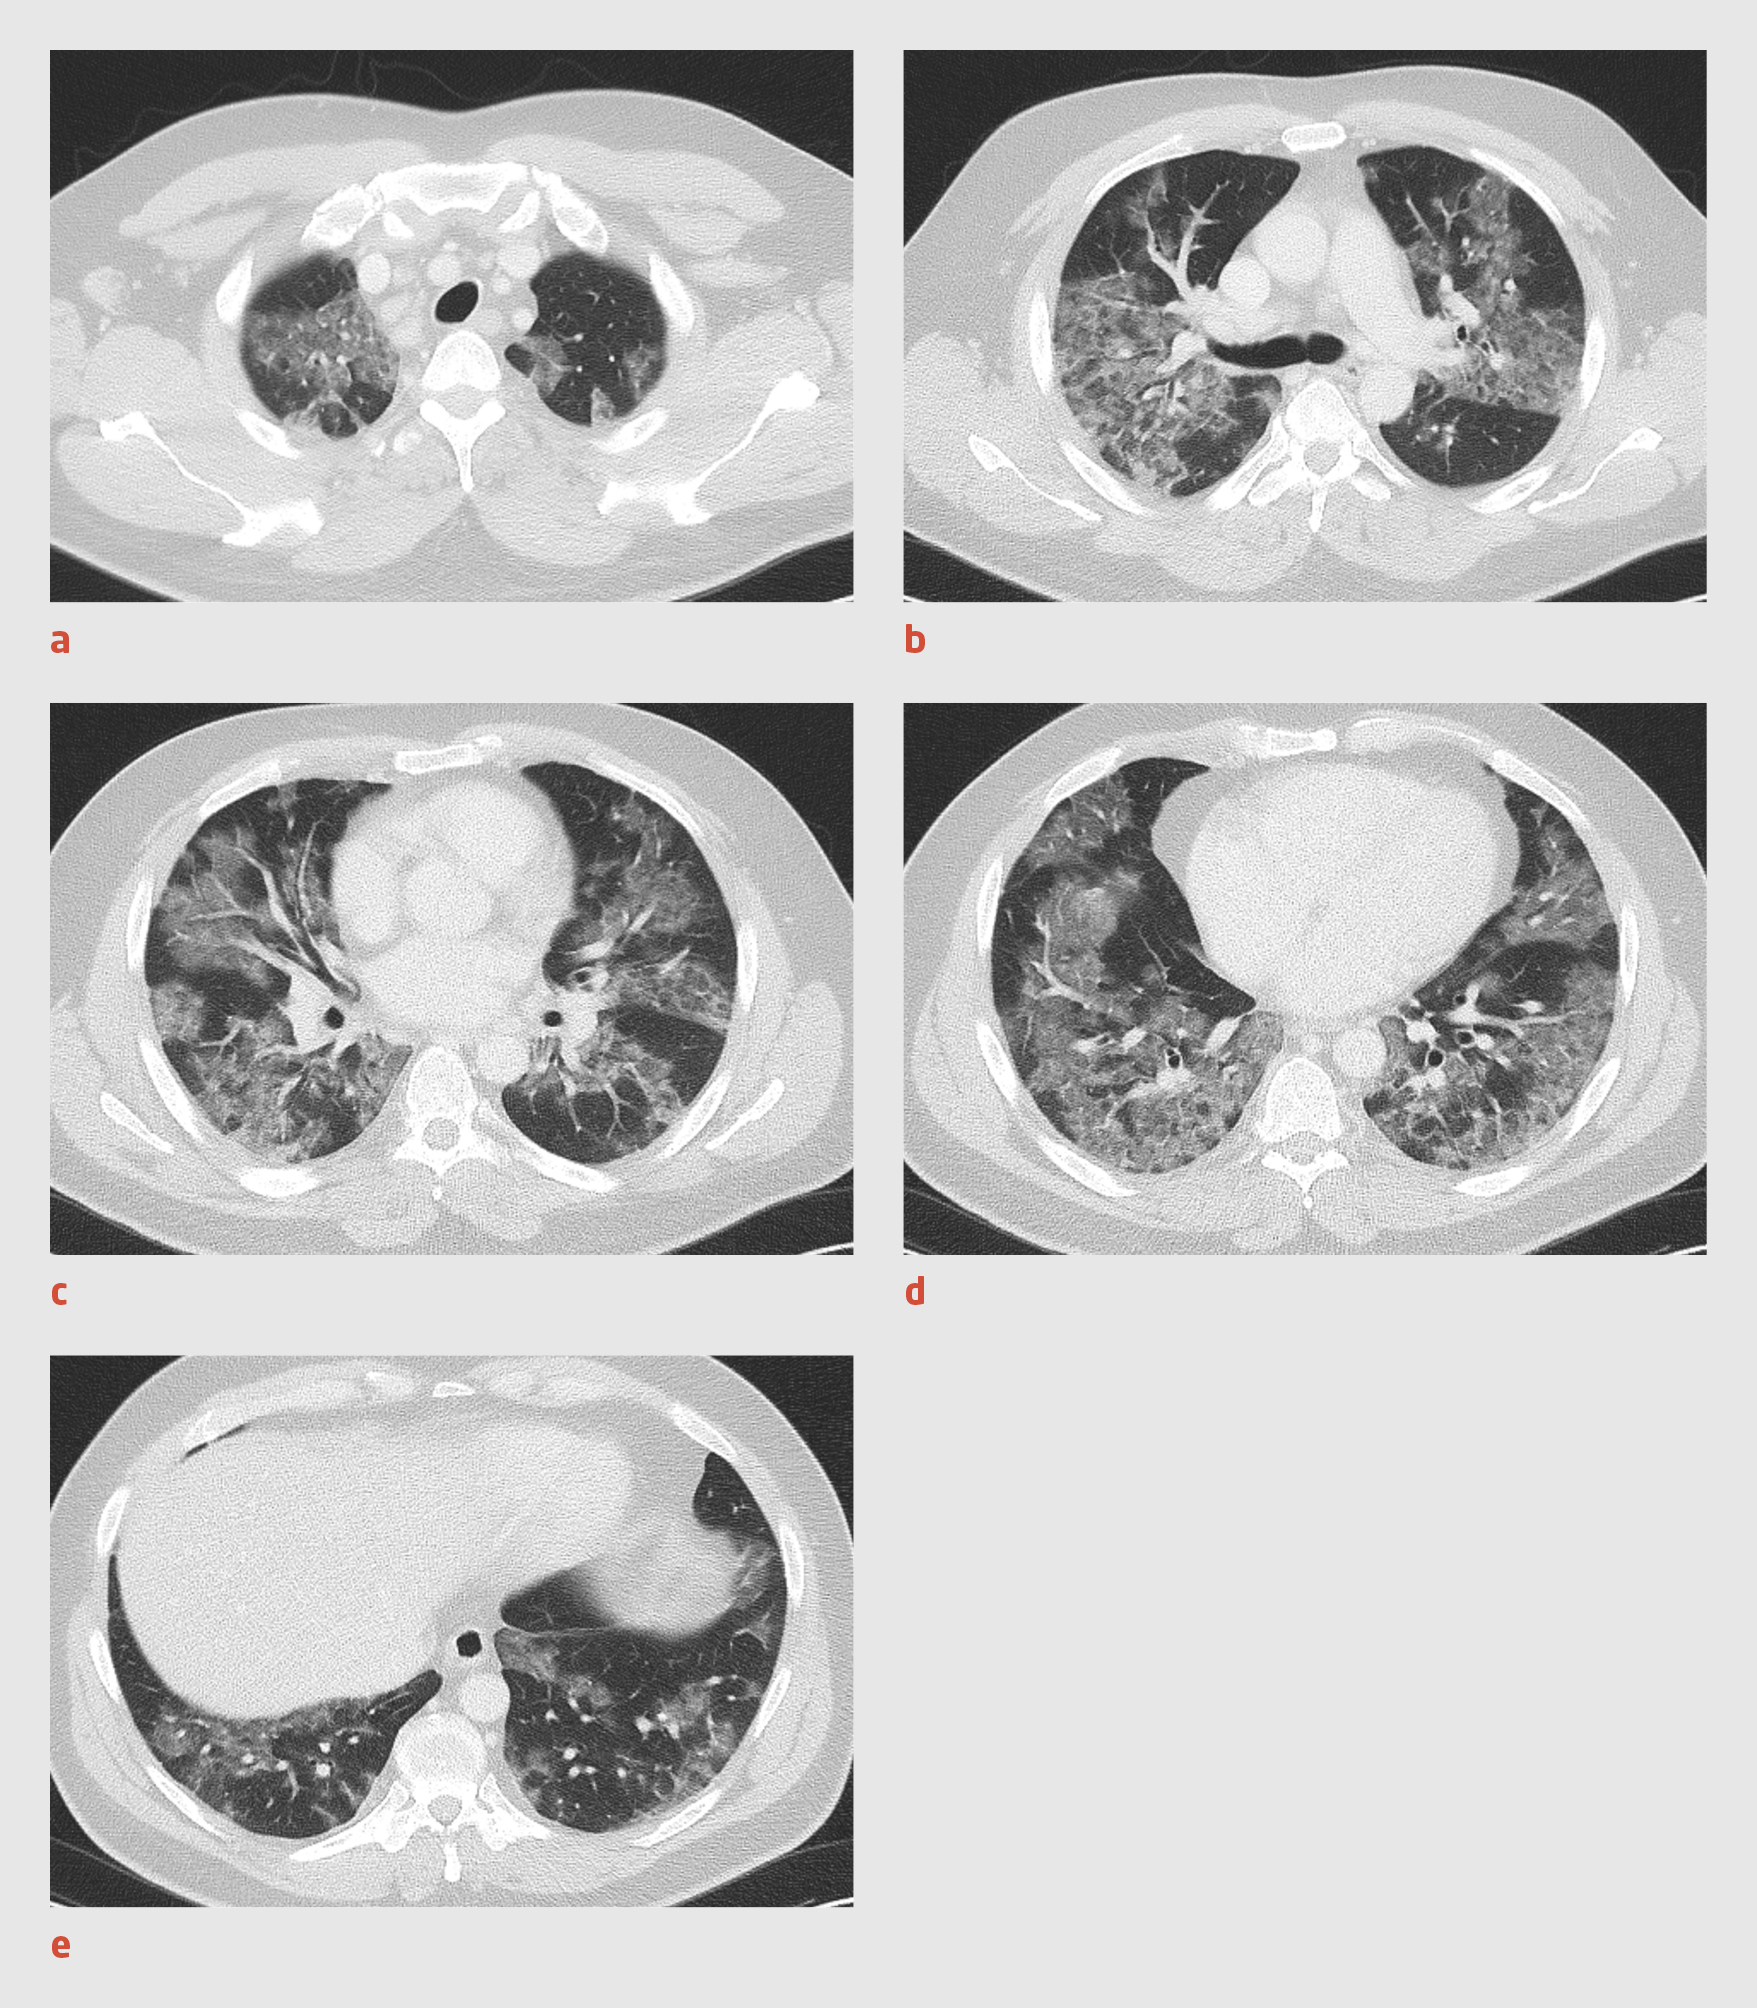

Bij de 12 patiënten die tot en met 13 maart werden opgenomen op de IC was 75% van de thoraxfoto’s bij opname afwijkend. Bij 4 patiënten, die uiteindelijk allemaal in de periode tot en met 13 maart op de IC werden opgenomen, werd bij opname een CT van de thorax verricht. Bij 1 patiënt werd de thoraxfoto niet-afwijkend afgegeven en toonde de CT-scan wel een consolidatie. Voor de overige 3 CT-scans was de bevinding conform de thoraxfoto, waarbij de meest kenmerkende bevindingen diffuus verspreide peribronchiale centrale en perifere matglas afwijkingen waren (figuur 2). Daarnaast was er bij 1 van de CT-scans sprake van minimale mediastinale lymfadenopathie.

Figuur 2

Afwijkingen op CT-scan bij COVID-19

Figuur 2 | Afwijkingen op CT-scan bij COVID-19

CT-scans van 1 van de 29 eerste patiënten met COVID-19 uit een ziekenhuis in Noord-Brabant met diffuus verspreide peribronchiale centrale en perifere matglas afwijkingen.